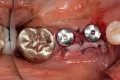

Установка имплантатов Osstem в сочетании с направленной костной регенерацией (методика «сэндвич»)

По данным ряда клинических исследований, для успешного отдаленного прогноза имплантации и эффективной профилактики костных дефектов толщина вестибулярной и язычной костных стенок в области имплантата должна быть не менее 1 мм. Обнажение поверхности имплантата в связи с ограниченной толщиной альвеолярного гребня может привести к рецессии десны и ухудшению внешнего вида улыбки. Кроме того, пациент может испытывать трудности при поддержании гигиены полости рта, что в свою очередь повышает риск развития периимплантита. Существуют хирургические методики увеличения толщины кости одновременно с установкой имплантатов. Среди них особой популярность пользуется направленная костная регенерация (НКР).